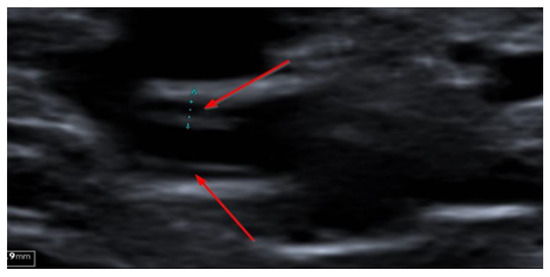

2. Case Presentation